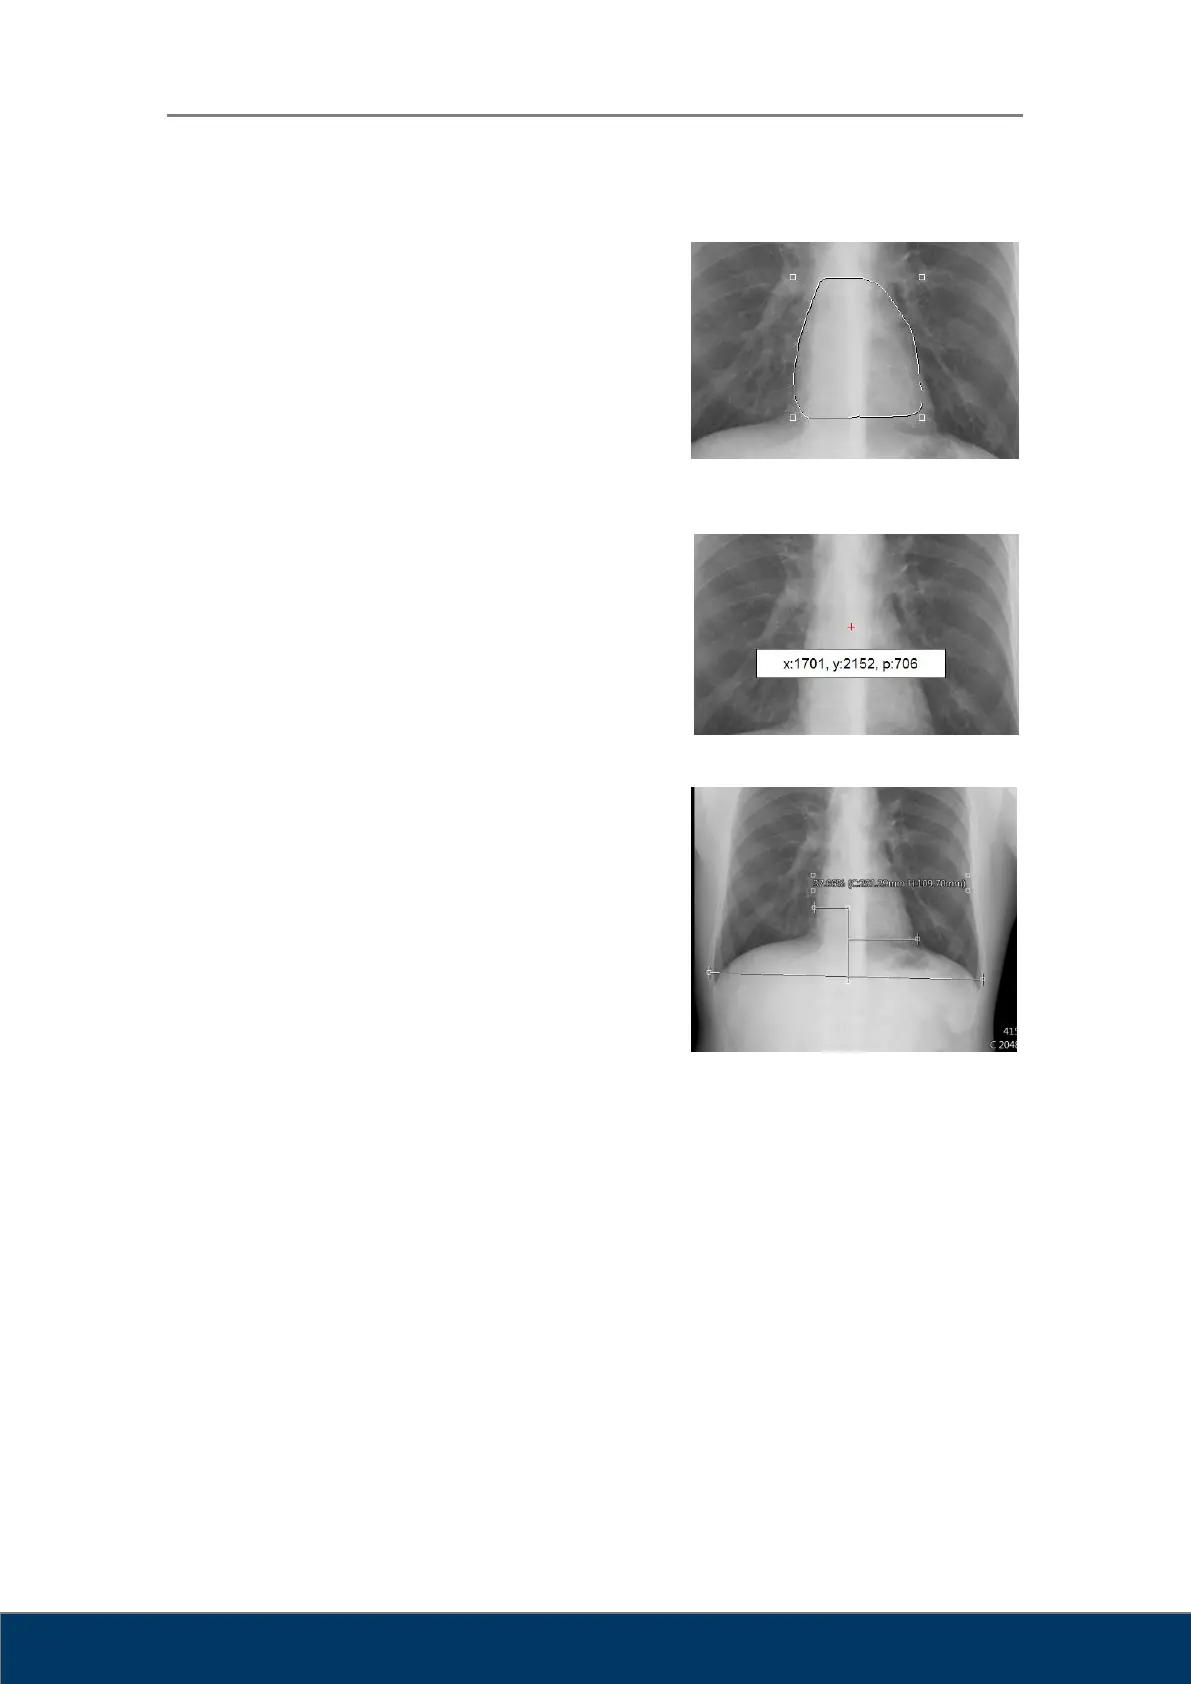

Crea una selección de dibujo libre. Haga clic y

arrastre el cursor hasta que consiga la forma que

desee. Suelte el botón del ratón cuando haya

terminado de dibujar. Puede hacer clic dentro de

la selección para desplazar la selección de dibujo

libre.

Mide el valor de xeles. Haga clic y arrastre el

cursor para que aparezcan en la pantalla las

coordenadas (x, y) y los valores de xeles (p) de

la posición del cursor.

Mide la proporción entre las áreas cardiaca y

torácica.

1. Haga clic en el punto final izquierdo del tórax.

2. Haga clic en el punto final derecho del tórax.

3. Desplace el punto de control superior

izquierdo al punto final izquierdo del coran.

4. Desplace el punto de control superior

derecho al punto final derecho del coran.

5. El valor de medición aparecerá en forma de porcentaje.